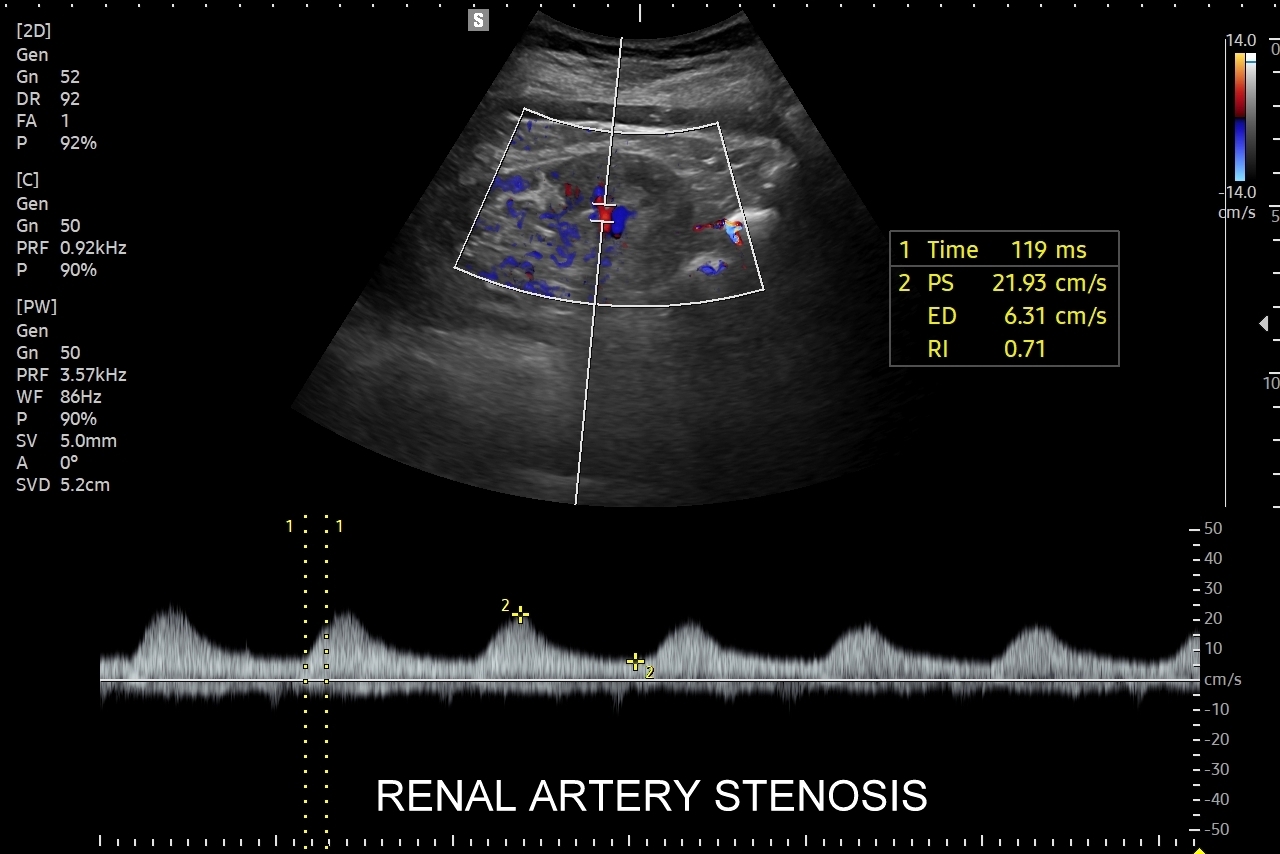

Doppler przepływów nerkowych (USG przepływy nerkowe) jest połączeniem badania obrazowego USG z badaniem funkcjonalnym nerki, jej naczyń tętniczych i żylnych oraz globalnie stanu układu krążenia. Najczęstszym wskazaniem do wykonania USG Doppler tętnic nerkowych, będącego częścią USG Doppler przepływów nerkowych, jest nadciśnienie tętnicze i poszukiwanie jego przyczyn w postaci zwężenia tętnic nerkowych, które mogą wystąpić w odcinku przednerkowym, jak i wewnątrznerkowym. Wykonanie oceny dopplerowskiej nerki jest szczególnie ważne w przypadku wystąpienia nadciśnienia tętniczego u osób młodych lub u dzieci.

Inne wskazania do przeprowadzenia diagnostyki USG przepływów nerkowych obejmują ocenę funkcji nerek w przebiegu chorób ostrych oraz przewlekłych, takich jak nefropatia cukrzycowa, glomerulopatie, czy zapalenia kłębuszków nerkowych. Badanie USG Doppler wykonywane jest również przy podejrzeniu zakrzepicy żyły nerkowej i zespołu „dziadka do orzechów”; przy stwierdzeniu obecności żylaków powrózka nasiennego u mężczyzn; żylaków miednicy u kobiet; w sytuacjach, gdy podczas standardowego badania USG jamy brzusznej uwidoczniono patologię nerki (np. guz nerki, marskość); a także przy stwierdzeniu podwyższonych wartości parametrów nerkowych w badaniach laboratoryjnych (kreatynina, mocznik, cystatyna C, potas) oraz w ramach oceny USG nerki przeszczepionej.